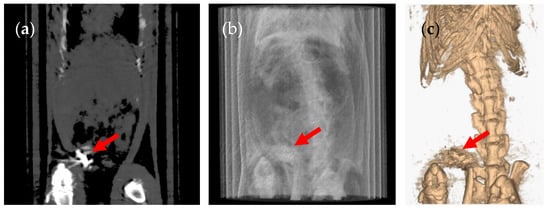

3. Results and Discussion